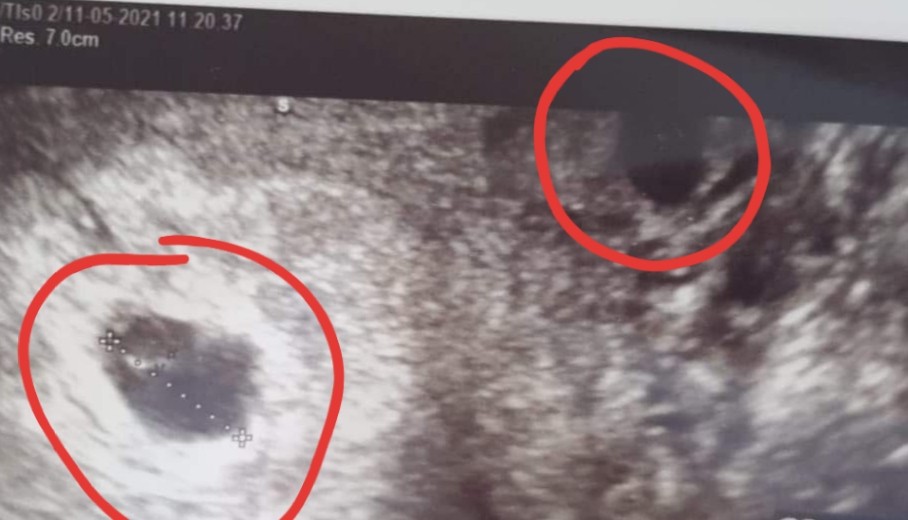

Hej mamusie. Powiedzcie mi czy tutaj jest jedenczy dwa pęcherzyki ? Z pierwszej wizyty w 5 tygodniu i drugie usgz 6 tygodnia. Ginekolog nic nie wspomniał żesą dwa za to przepisał duphaston i luteine. Czy tylko ja tam widzę dwa ?

chyba trochę za duza ta odległość. Może to jakiś krwiaczek ja tez miałam czarna plamę na USG nad pecherzykiem właściwym właśnie w 5t to lekarz mówił że nie wie co to może będę z tego krwawić. Ale minęło i na razie cisza.

nie znam się ale może to krwiaczek ? Z tego co pamietam na moim usg wyglądał podobnie do pęcherzyka 🙈 przynajmniej dla mnie 😉

Myśle ze lekarz powiedziałby Ci o drugim pęcherzyku, to dość istotne 😉